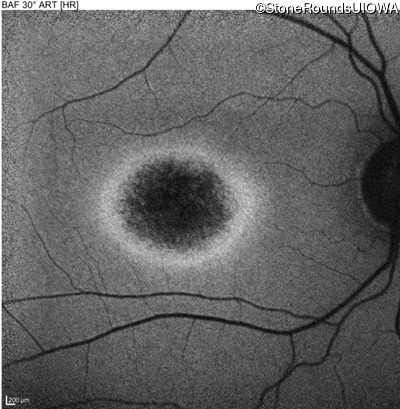

Age at visit: 17 years

This 17 year old male was correctable to 20/30 OU when he got his first glasses at age 5. At age 13 his best corrected vision was 20/40 OU. He feels that his color vision has always been poor.

Age at visit: 17 years (Visit 2)

Age at visit: 21 years

Age at visit: 23 years

Age at visit: 25 years